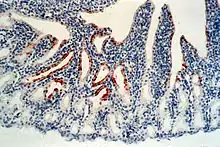

Lésions

Les lésions varient selon les cas. Elles sont proches de celles induites par l'influenza aviaire :

- œdème des tissus interstitiels ou péritrachéaux (cou) notamment à la hauteur du bréchet, accompagnés parfois d'hémorragie de la muqueuse trachéale, de pétéchies (taches rouges) et d'ecchymoses sur la muqueuse de l'estomac glandulaire, autour des glandes à mucus

- œdème, hémorragies, nécrose et/ou ulcérations du tissu lymphoïde de la muqueuse intestinale

- œdème, hémorragies ou dégénérescence des ovaires